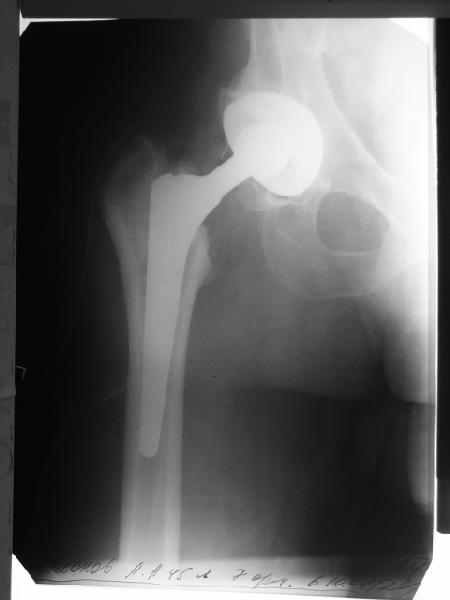

Мужчине 1963 г.р. в октябре прошлого года в Кургане сделано эндопротезирование правого тазобедренного сустава (последствия перелома шейки бедра) бесцементным протезом Cerafit.

Госпиталирован по месту жительства (МСЧ г. Новоуральск). Уложен на скелетное вытяжение. На снимках от 3 февраля видно миграцию ножки в дистальном направлении, она явно нестабильна. В нашей больнице вряд ли что-то удастся сделать. Сопутствующих заболеваний нет. Хотелось бы получить совет по тактике. Если нужно ревизионное протезирование, куда лучше пациента направить? Спасибо.

Уважаемый Валерий Павлович! Отправляйте больного к нам,в Курган, где он и был первично оперирован. Надо реимплантировать ножку, возможно ревизионную + остеосинтез проволокой. Для транспортировки фиксировать в кокситной повязке.

У пациента перипротезный перелом бедра тип 2Б по ванкуверской классификации.

Показано ревизионное протезирование с заменой ножки. Вероятно в Курган. Можем принять на лечение, но при наличии источников финансирования - дорого.